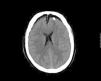

La presencia de aire dentro de la cavidad intracraneal es una entidad rara que se conoce con el nombre de neumoencéfalo y en la mayoría de los casos no presenta repercusión clínica salvo cuando ocasiona un aumento de la presión intracraneal que puede llegar a producir un deterioro del nivel de conciencia, coma e incluso la muerte.

Presentamos un caso, poco frecuente, de un varón joven sin antecedentes personales de interés que ingresa en una unidad de cuidados intensivos para vigilancia tras un accidente de tráfico con traumatismo craneoencefálico asintomático y con tomografía computarizada craneal de ingreso «sin hallazgos significativos». Durante su estancia en la unidad de cuidados intensivos se aplica presión positiva en la vía aérea con ventilación mecánica no invasiva que genera entrada de aire en la cavidad intracraneal (neumoencéfalo) que condiciona deterioro neurológico importante con necesidad de cirugía urgente.

The presence of air inside intracranial cavity is a rare entity known as pneumocephalus and in most cases doesn¿t present any clinical repercussion except in case of elevated intracranial pressure that can lead to a decreasing level of consciousness, coma and even death.

We present a rare case of a young male, without medical precedents of interest, hospitalized in an intensive care unit for vigilance after a traffic accident with asymptomatic crane encephalic trauma and cranial computerized tomography without meaningful findings. During the intensive care unit stay positive pressure is applied in airway with non-invasive mechanical ventilation that produces air entrance in cranial cavity (pneumocephalus) causing neurological deterioration and necessity of urgent surgery.